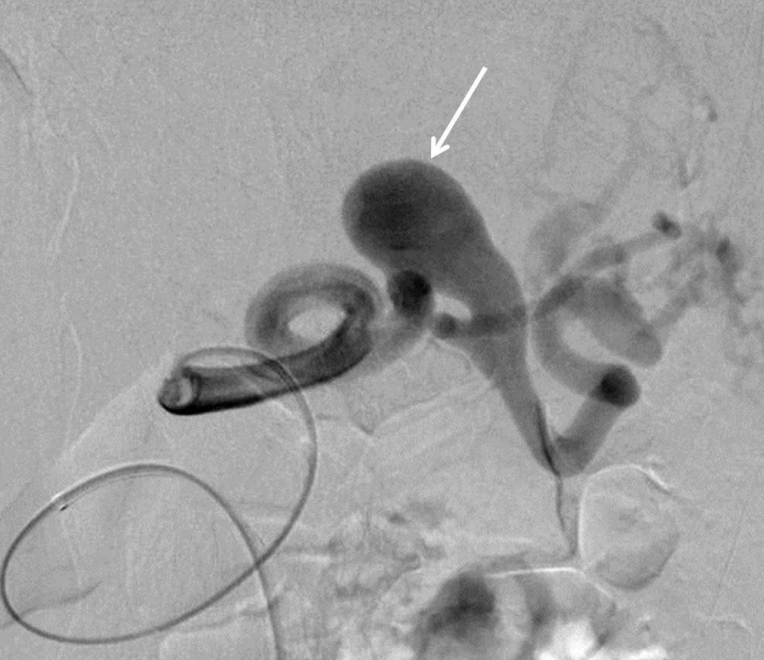

Fig. 3

Radiographs obtained during embolization. One of distal branch of splenic artery was embolized with IDC coils (arrow in A). The distal neck of aneurysm was embolized by multiple IDC coils (arrow in B), which was anchored to the small distal branch of splenic artery. Further embolization of proximal neck and part of aneurysmal sac was done (arrow in C).